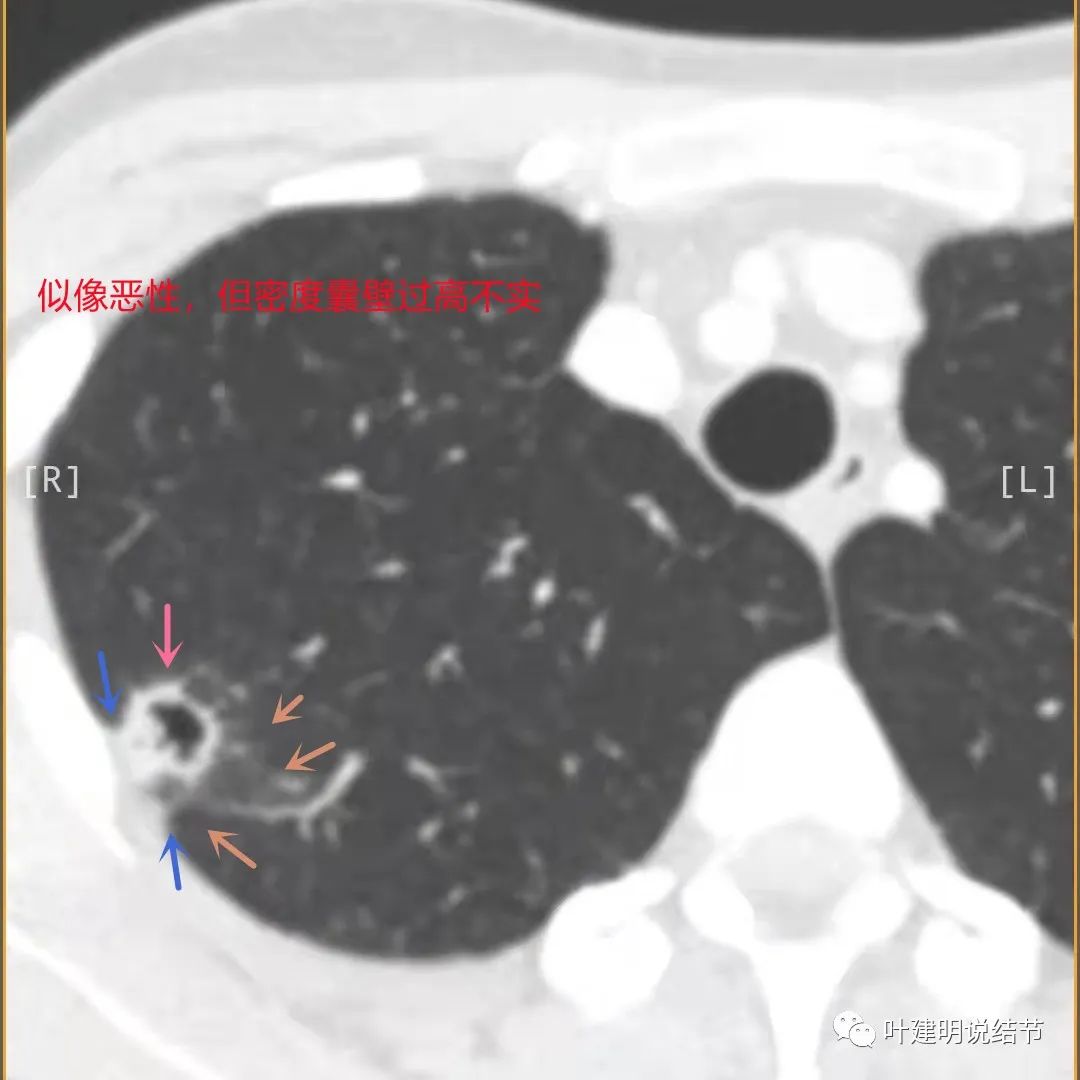

上图也像恶性,但整个囊壁的密度感觉过高了点,边缘磨玻璃淡、散且模糊,邻近胸膜有增厚

上图病灶的边相对比较光,没有毛刺征,邻近胸膜增厚

上图病灶边缘比较平直,没有膨胀性(桔色箭头),旁边的磨玻璃影淡且界限不清,邻近胸膜增厚。